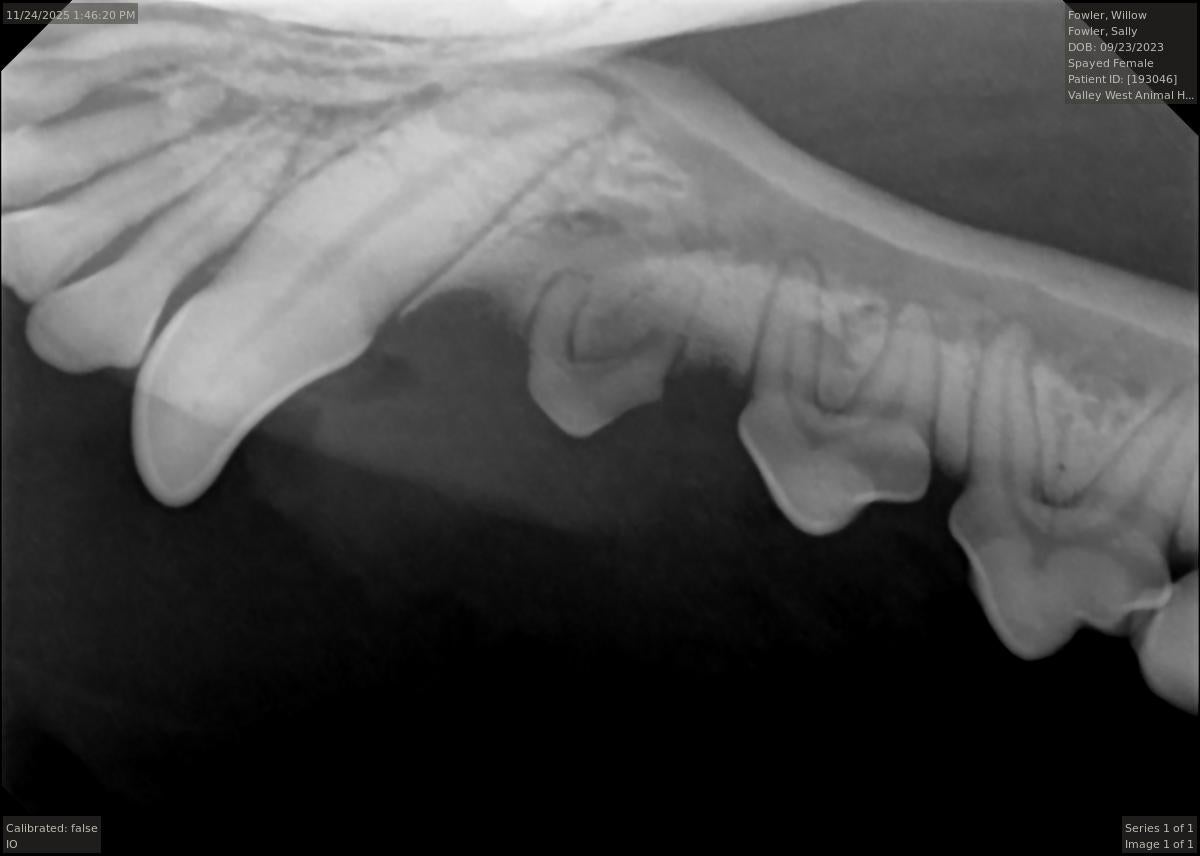

In order to remove this tartar, we perform dental scaling, our most basic dental procedure. During the scaling process our practice uses sonic and ultrasonic power scalers as well as hand held instruments to remove this tartar from the surface of the teeth both above and below the gum line.

Tooth extraction is another very common procedure. It is the goal of our practice for your pet to retain as many teeth as possible. However, sometimes extraction is the only option to relieve pain or ensure that periodontal disease does not advance. If not extracted, many times a diseased tooth can compromise the surrounding tissue and neighboring teeth. If caught early, there are more treatment options available for periodontal disease.